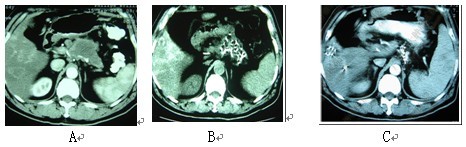

图2 男性,61岁。胰腺体尾部腺癌伴肝转移。A:治疗前;B:冷冻-碘粒子联合治疗后1个月复查;

C::治疗后6个月复查。血液CA19-9降至40IU以下。患者生存27个月。

图3 女性,59岁。胰腺头部4X4 cm病变,活检显示未分化腺癌。A:治疗前;B:冷冻-碘粒子治疗后12个月复查PET-CT,原先病变无明显活性,但在胰腺体部出现新病变,给予冷冻治疗;C:3个月后复查PET-CT,病变活性抑制。患者生存28个月。